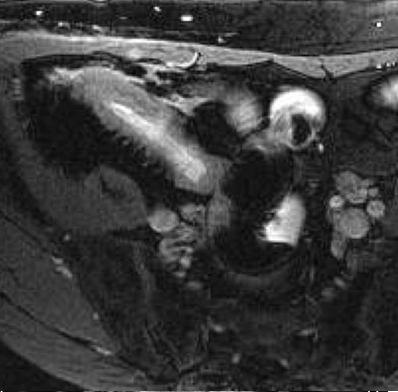

| Maladie de Crohn , Image

epaissisement de la paroi de ileon avec aspect stenosant de

la lumen ( fleche rouge ) . Image IRM en

coupe coronal |

Portion stenosant de ileon avec

epaissisement de la paroi . Dilatation de l'intestin

en amont peut se voyait ( fleche rouge ) .

Image IRM en coupe axiale |